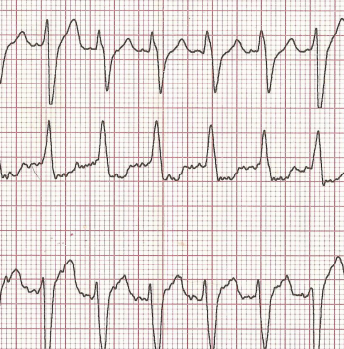

Vous le savez certainement, le canton de Fribourg est précurseur en terme de "premiers répondants" équipés d'AED permettant de prodiguer le plus précocement possible, les premiers soins aux victimes d'arrêts cardio-resp…